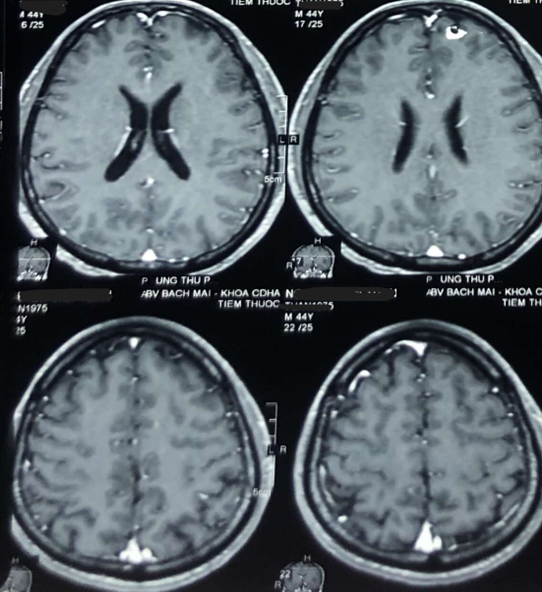

Chụp Cộng hưởng từ sọ não (4/4/2019):

Hình 1:  Hình ảnh chụp MRI sọ não: Nhiều nốt ngấm thuốc mạnh rải rác ở nhu mô não trên và dưới lều, theo dõi tổn thương thứ phát (mũi tên đỏ).